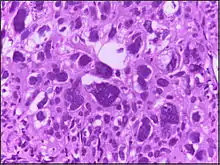

![]() | Malignant melanoma | Malignant spindle cell neoplasm, showing numerous mitotic figures, including atypical tripolar mitotic figure, in the centre. | Category: Histopathology of melanoma | Malignant melanoma |